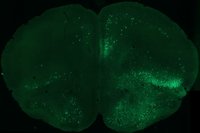

Schackmatt är ett dans/scenkonstverk som har sin bas i neurovetenskapen där olika verktyg och metoder inom neurologisk forskning tillämpas. Mari Vittradotter Johansson vill skapa flera dimensioner där tankar, känslor och fysiska uttryck går in och ut ur varandra som logiska, absurda situationer och mindfucks. Inom neurovetenskaplig forskning finns idag tekniken att styra specifika grupper av nervceller som påverkar beteendet. Denna möjlighet är en stor inspiration till att forma detta verk som startar sin process hos Atalante Transit-residens.